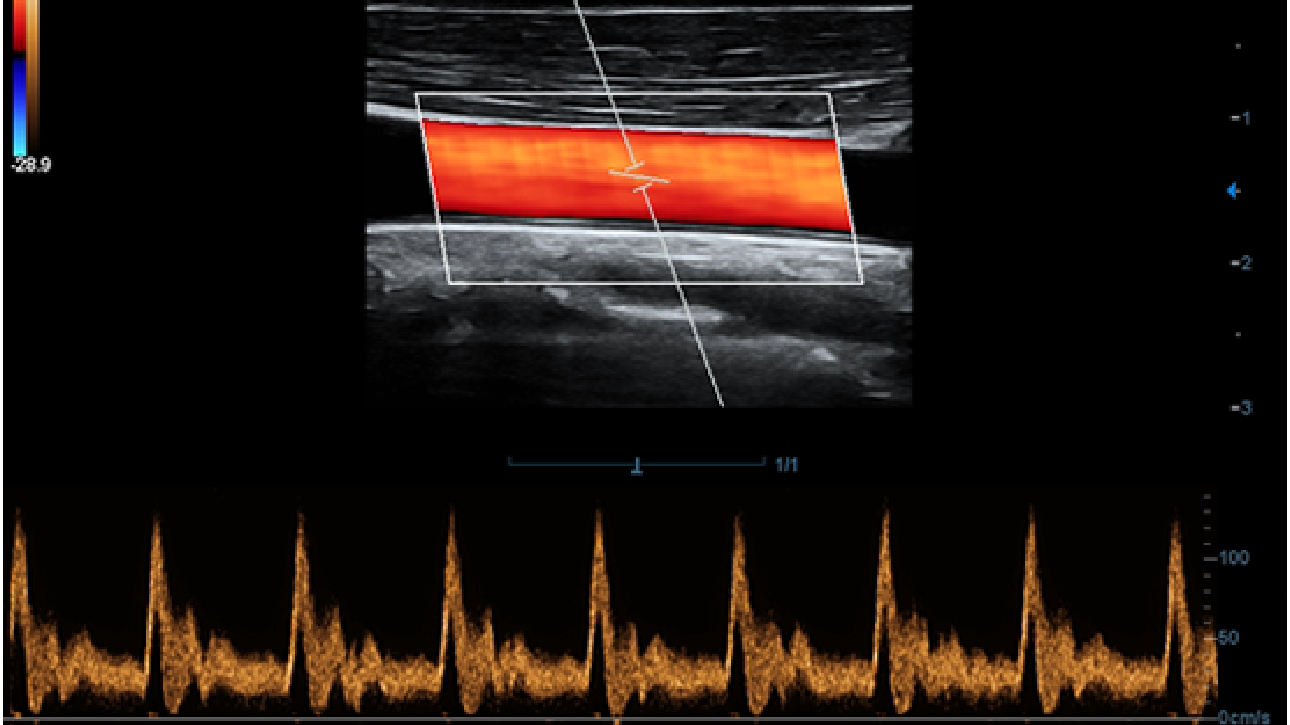

X-Insight, daha geli?mi? g?rĂŒntĂŒler elde etmek i?in kapsaml? bir ??zĂŒmdĂŒr.

Mindrayâin yeni ??zĂŒmĂŒ, geli?en en yeni ultrason teknolojileri ile birlikte, mĂŒ?terilerin g?rĂŒ?lerini klinik gerekliliklerle tam anlam?yla birle?tiren bir ??zĂŒmdĂŒr. Taptaze bir ruhla, gelece?e odaklanarak ve s?n?rs?zl???n pe?inde ko?arak, artan ?l?eklenebilirlikte sĂŒrekli olarak geli?en bir ??zĂŒmdĂŒr.

?ok y?nlĂŒ bir partner olarak, X-Insight'l? DC-60 Exp, her y?nĂŒyle gĂŒnlĂŒk klinik uygulamay? kolayl?kla ve belirsizlik olmadan y?netmenize yard?mc? olacak kapsaml? bir ??zĂŒm sunar.

MĂŒ?teri gereksinimlerine y?nelik g?rĂŒ?ler temelinde, X-Insight'l? DC-60 Exp, eXpress Clarity, eXceptional Intelligence ve eXceeding Experience ile gĂŒ?lendirilerek, hassas g?rĂŒntĂŒlemeyle yĂŒksek verimlilik sa?layacak ?ekilde tasarlanm??t?r.